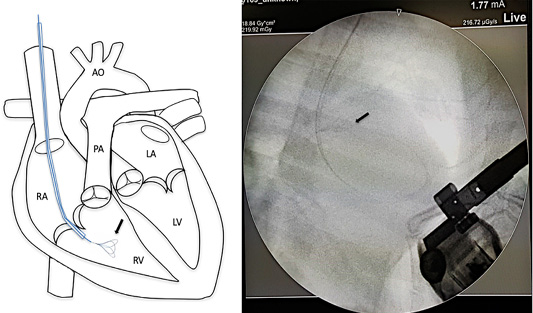

Mini vascular snare device (black arrow) with working space 4-8 millimeter was inserted into the right cardiac chamber with fluoroscopic guidance.